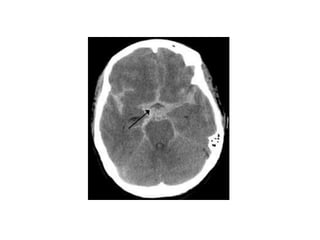

Cerebellar strokes

• Cerebellar strokes commonly impair balance

and coordination. Assess for ataxia

(incoordination) by having the patient extend

the index finger and then alternately touch

your finger and his or her nose. Do this on

both sides.

Cerebellar strokes • Cerebellarstrokes commonly impair balance and coordination. Assess for ataxia (incoordination) by having the patient extend the index finger and then alternately touch your finger and his or her nose. Do this on both sides.